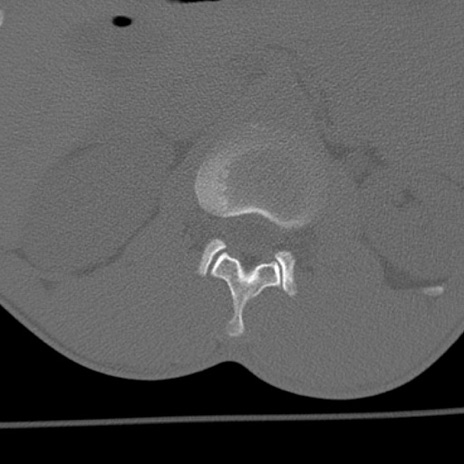

症例3 腰椎CT(横断像)

腰椎CT